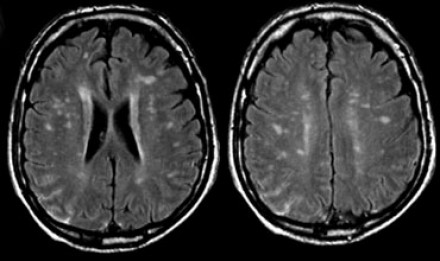

多發(fā)性增強病灶的鑒別診斷

圖片二

在上圖中,是各種多發(fā)性增強白質(zhì)病灶圖像,我們對其中部分病例進行詳細討論。需要說明的是,以下鑒別診斷中提到的疾病與上圖中的圖像并不完全重合。

血管炎

大多數(shù)血管炎性疾病的MRI成像特點是點狀增強。

腦部血管炎常見于系統(tǒng)性紅斑狼瘡、結(jié)節(jié)性多動脈炎(PAN)、白塞病(Behcet)、梅毒、韋格納肉芽腫(Wegener)、干燥綜合征(Sjogren)和原發(fā)性中樞神經(jīng)系統(tǒng)血管炎。

白塞病(Behcet)

白塞病更常見于土耳其患者。典型MRI表現(xiàn)是急性期出現(xiàn)腦干病灶結(jié)節(jié)性增強。

其他疾病的腦轉(zhuǎn)移病灶

其他疾病的腦轉(zhuǎn)移病灶周圍常包裹有水腫帶。

交界區(qū)腦梗死

周圍交界區(qū)腦梗死在病變早期可出現(xiàn)增強病灶。